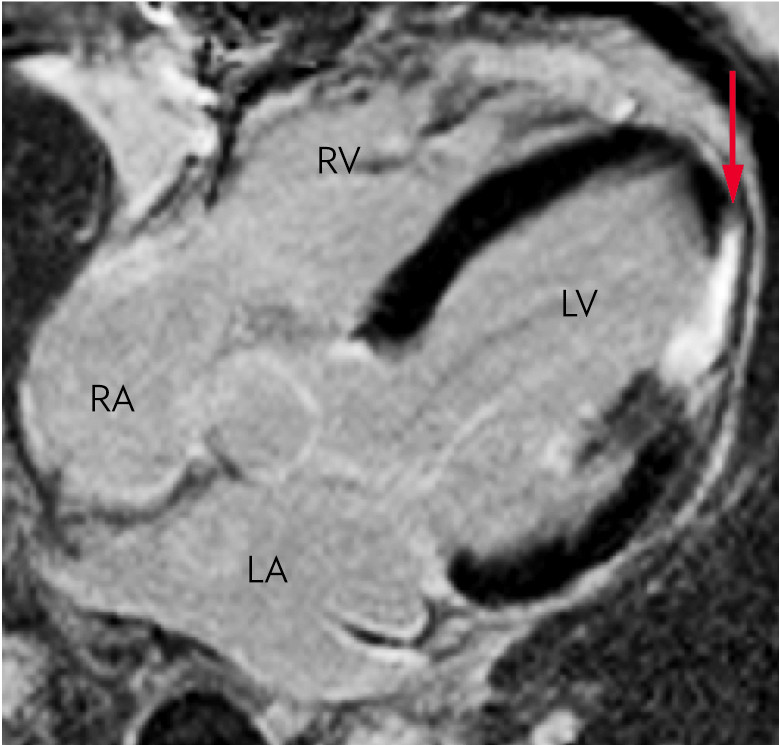

In replacement fibrosis, qualitative differences can be detected in late enhancement with gadolinium-based contrast mediums (10, 18). After myocardial infarction, increased late enhancement is seen, consistent with replacement fibrosis (Figure 5). In non-ischaemic cardiac muscle diseases, late enhancement is associated with increased hypertrophy and a worsened prognosis in several conditions (23, 24). It is important to be aware that the late enhancement method is unsuitable for assessing fibrosis in cases of diffuse fibrosis with a homogenous myocardium (15, 25).